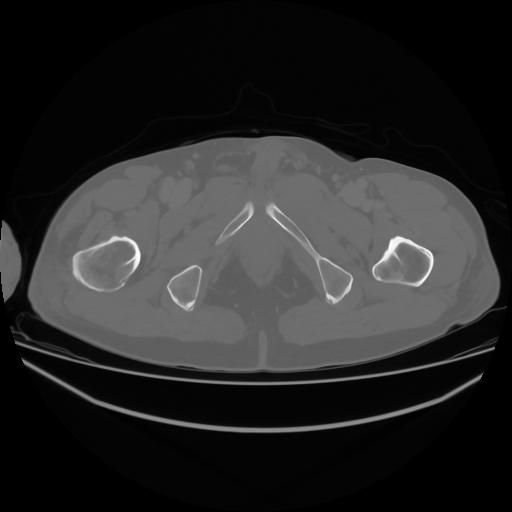

4 CUERPO,CE,Axial,3.0,CUERPO,,